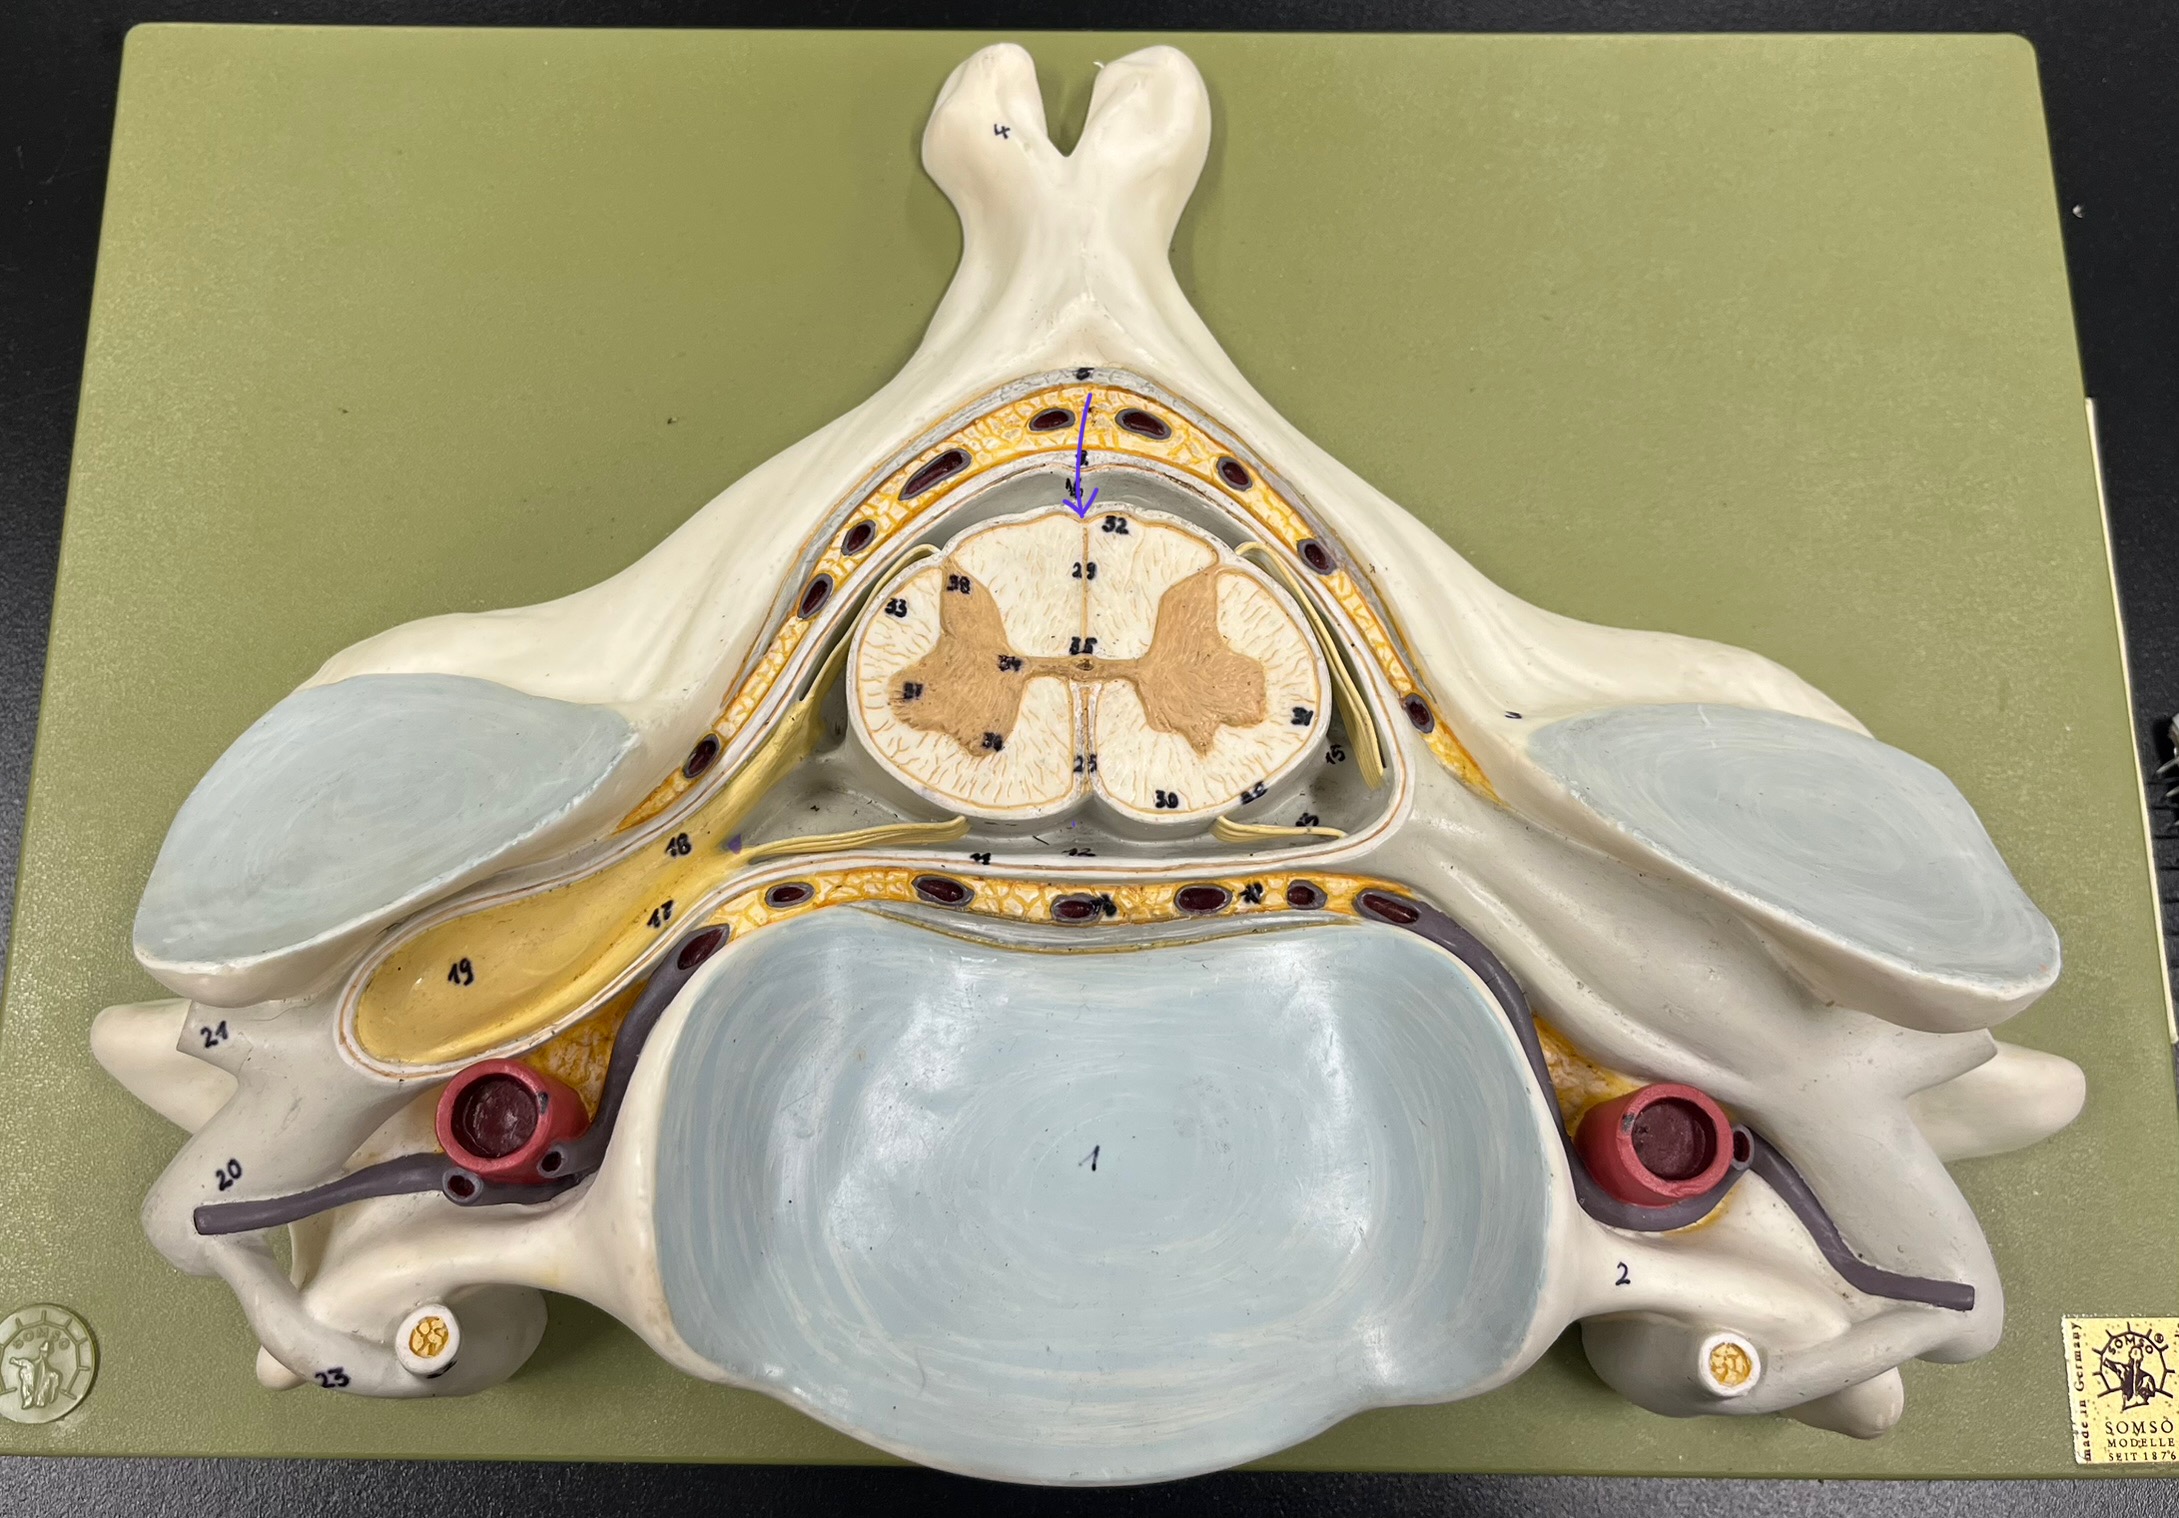

What is the groove here?

anterior median fissure

posterior median sulcus

central canal

posterior (dorsal) root ganglion

What is the bulb here?

posterior (dorsal) root ganglion

posterior (dorsal) root

posterior (dorsal) root

anterior (ventral) root

anterior (ventral) root